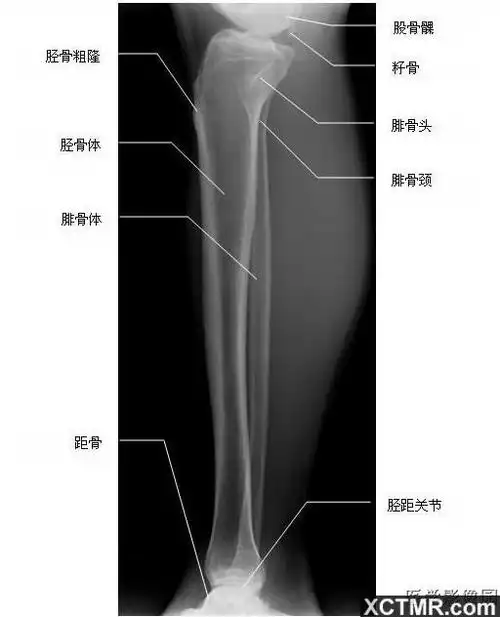

填图题胫腓骨解剖

胫腓骨侧位-x线-解剖图片